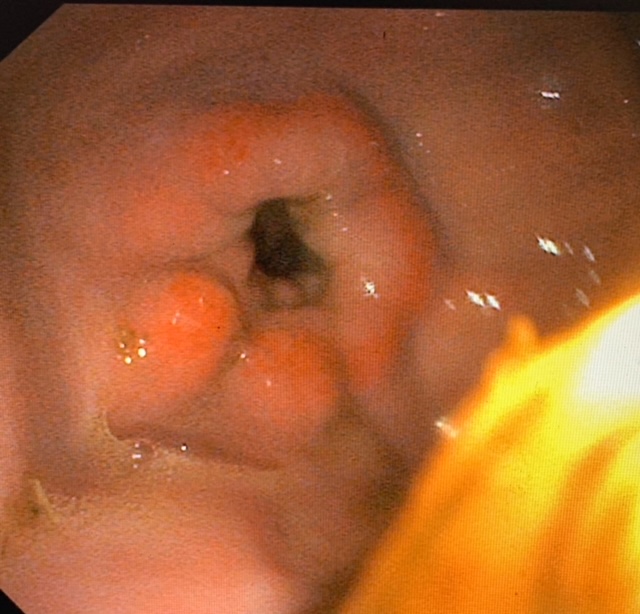

Gastroscopy is an essential diagnostic tool for the identification of Equine Gastric Ulcer Syndrome (EGUS) and Equine Glandular Gastric Disease (EGGD), a common cause of poor performance, weight loss, reduced appetite, and resistance to ridden work. It is the only reliable method to directly visualise the stomach and proximal duodenum, allowing accurate diagnosis and grading of gastric disease.

Gastroscopy involves passing a long endoscope through the horse’s nose, down the oesophagus, and into the stomach. Our 3.5m digital gastroscopes allow full visualisation of the stomach lining and the first part of the duodenum. Biopsies can be taken if required, enabling a precise diagnosis and tailored treatment plan. Horses must be fasted overnight before the procedure to ensure the stomach is empty for optimal imaging.

Our digital video gastroscopes capture high-quality images and allow image recording, which is invaluable for monitoring lesions over time and assessing response to treatment. Video gastroscopy enables complete examination of the oesophagus, squamous and glandular regions of the stomach, the pylorus, and the proximal duodenum. Repeat examinations can be performed to guide treatment and track healing.